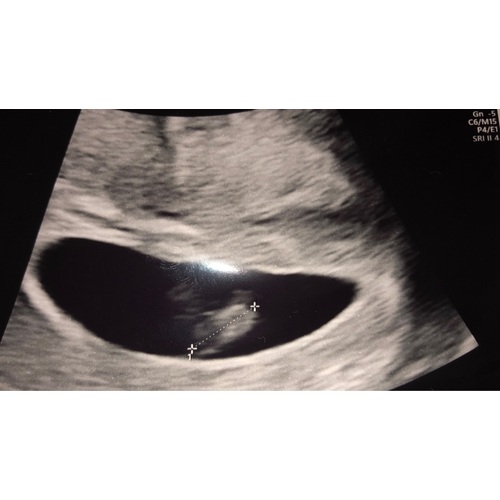

Wij hadden de 1e echo toen ik dacht 7 weken te zijn, dit bleek 5+5 te zijn. Met een inwendige echo het hartje zowel zien als horen kloppen. Verder noemde wij de baby in die weken nog een vlek omdat het eigenlijk niet meer dan dat was... Nu gelukkig al echt een mini mensje :-)

Ik heb toevallig een (inwendige) echo met 6+6 gehad! We hebben toen ook al het hartje gehoord.